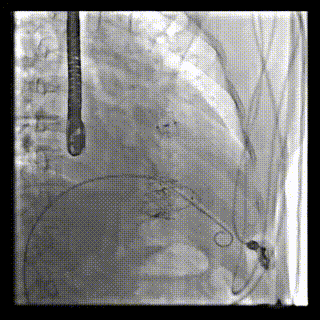

2021年12月24日,復(fù)旦大學(xué)附屬中山醫(yī)院葛均波院士團(tuán)隊(duì)成功應(yīng)用LuX-Valve Plus為一例極重度三尖瓣反流(TR)合并房顫、房缺的患者完成了經(jīng)血管三尖瓣置換術(shù),這是在前基礎(chǔ)上,本周完成的第三例經(jīng)血管三尖瓣置換手術(shù),葛均波院士、周達(dá)新教授等與心外科魏來(lái)教授、賴顥教授,心超室的潘翠珍教授、李偉教授及麻醉科的郭克芳教授共同完成了本周手術(shù),均獲得圓滿成功!患者術(shù)后超聲顯示無(wú)TR,臨床癥狀明顯改善。本周手術(shù)的成功也為L(zhǎng)uX-Valve Plus救治性臨床研究添上了濃墨重彩的一筆。

三例患者入院后,葛均波院士團(tuán)隊(duì)周達(dá)新教授、潘文志教授、張?jiān)床┦?、陳莎莎博士及心超室的潘翠珍教授、李偉教授?duì)患者的情況進(jìn)行詳細(xì)評(píng)估和討論,最終決定為三例患者選擇LuX-Valve Plus40mm、50mm和50mm型號(hào)的瓣膜進(jìn)行手術(shù)治療。手術(shù)后即刻拔除氣管插管,術(shù)后患者三尖瓣反流癥狀得到顯著改善,復(fù)查心超結(jié)果顯示人工三尖瓣瓣膜支架固定穩(wěn)定,瓣葉關(guān)閉形態(tài)未見異常,未見明顯反流。